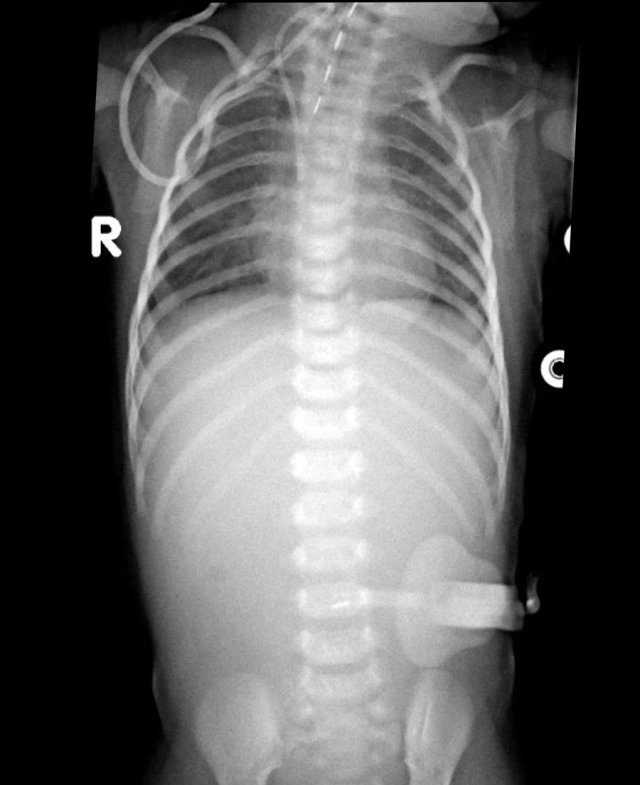

Here images of a neonate who developed NEC.

At this early stage the radiograph only shows non-specific bowel dilatation.

At this stage you cannot make the diagnosis.

Here another typical case of NEC.

Notice the air in the portal vein (arrow) and peripheral portal branches.

This is seen on the X-Ray and on ultrasound.

In this patient with NEC notice all the airbubbles in the wall of the bowel and within the liver.

Pneumoperitoneum in severe NEC.

Air can be seen on both sides of the bowel wall.

This is called the Rigler sign.